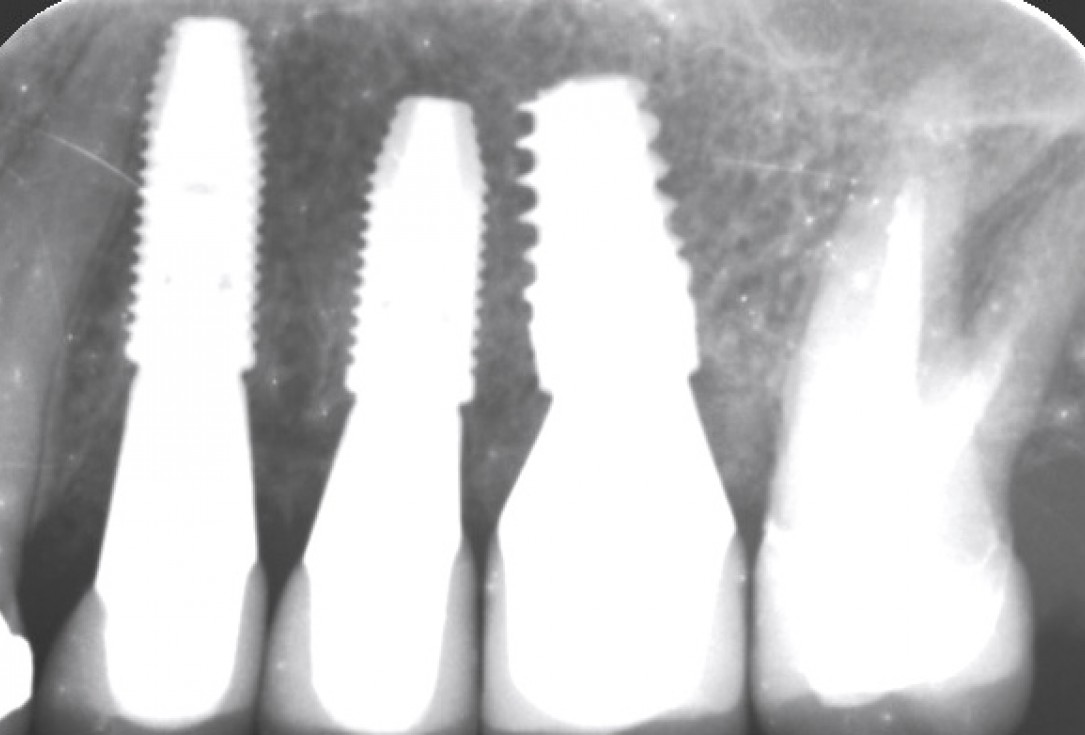

13/13 - Control x-ray image of the placed implants after 7 months

Multiple socket preservation in the maxilla with collacone® max – Dr. D. Jelušić